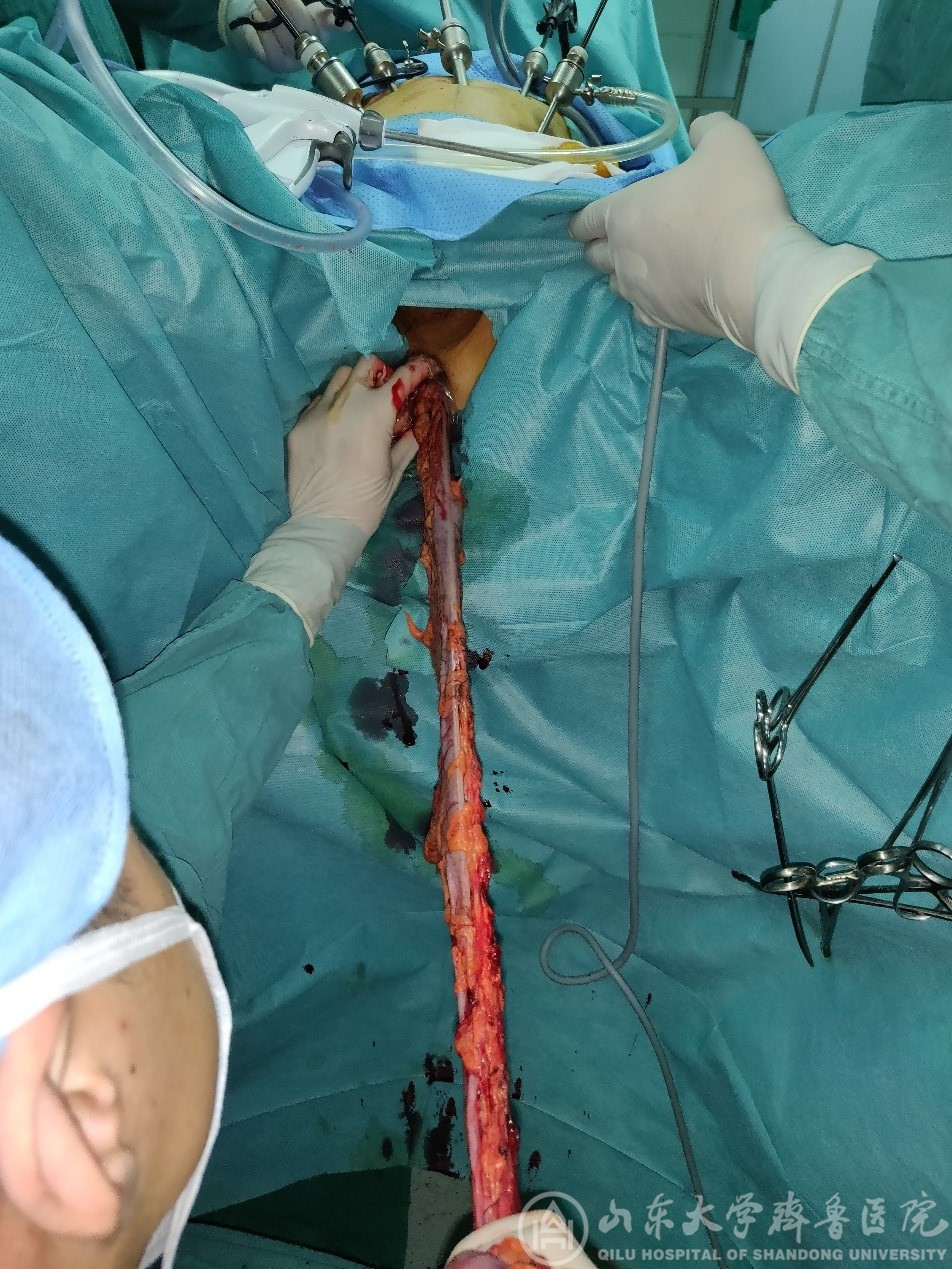

患者一,女性46岁,术前诊断为乙状结肠癌并肝转移;患者二,男性,65岁,术前诊断为结肠慢传输型便秘。在完善术前检查及充分的术前准备之后,在高磊医师、梁亚航医师、肝脏外科杜刚医师、麻醉科、手术室人员的协助下,分别成功完成腹腔镜下结肠癌肝转移一期切除和保留回盲部结肠次全切除NOSES手术。手术过程顺利,术中基本无出血,手术标本经直肠及肛门取出,腹部无辅助切口。

传统的腹部手术,都需经腹部切口取出切除的手术标本。即使是常规的腹腔镜微创手术,在完成腹腔镜下组织的游离和切除后,也同样需要在腹部取一个5厘米左右长度的切口,用来取出标本。经自然腔道取标本手术(NOSES手)是借助腹腔镜手术的技术平台,在腹腔镜手术的基础上完成手术标本的分离及切除,最后经过人体的自然腔道(如肛门、阴道、口腔等)取出切除的标本。除腹腔镜手术操作的几个微小戳孔之外,腹部无需另取切口。NOSES手术的优势在于可以减轻痛苦,加速康复,除了能避免切口感染、切口疝等并发症之外,在美观上也更符合患者的需求。